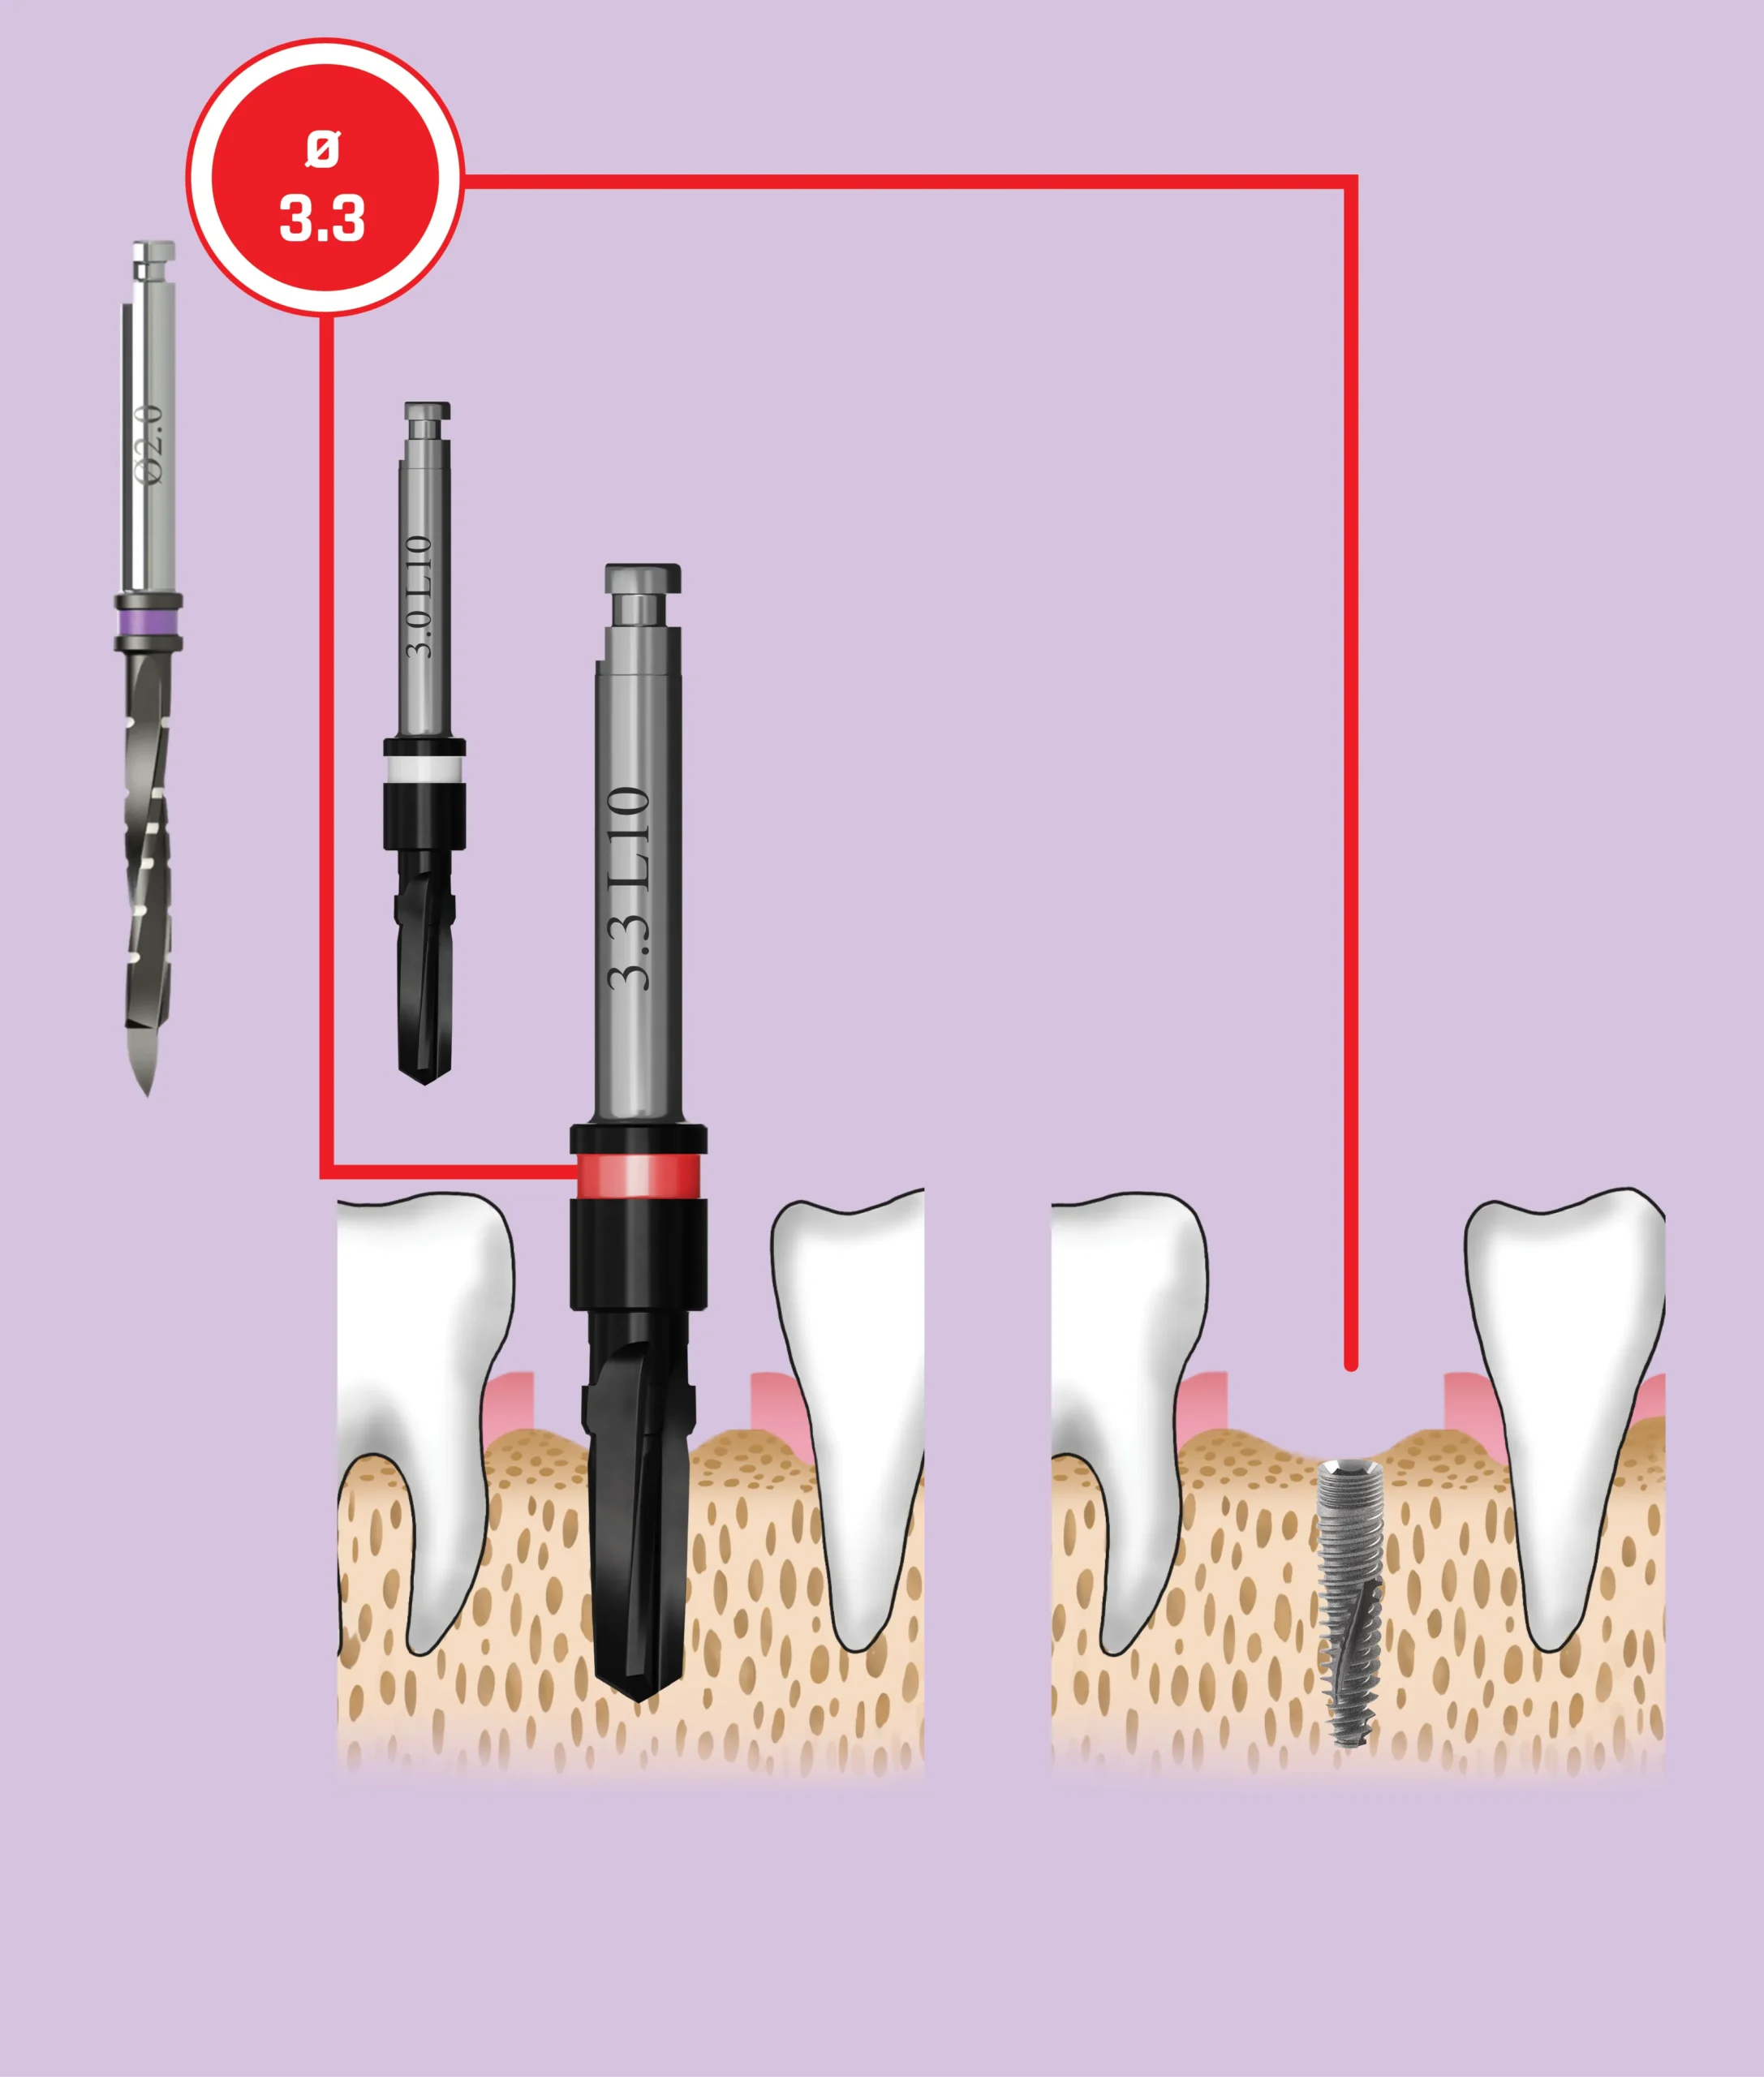

Quy trình mũi khoan

Nên sử dụng mũi khoan mồi 2.0 mm cho tất cả các đường kính implant. Các implant có đường kính 3.0 mm và 3.3 mm (Dòng Hẹp – Narrow Line) cùng với implant đường kính 3.75 mm (Dòng Tiêu Chuẩn – Standard Platform) nên được đặt ngang mức đỉnh xương. Các implant đường kính 4.2 mm, 5.0 mm và 6.0 mm (Dòng Tiêu Chuẩn – Standard Platform) có thể được đặt dưới mức đỉnh xương

| Đường kính Implant | 3.0 mm | 3.3 mm | |

|---|---|---|---|

| Mã màu | white | red | |

| Tổng số mũi khoan | 2 | 3 | |

| Mũi khoan cuối cùng | 2.5 mm | 2.8 mm | |

| Mũi khoan lớn nhất phù hợp với đường kính Implant | 2.5 mm | 2.8 mm | |